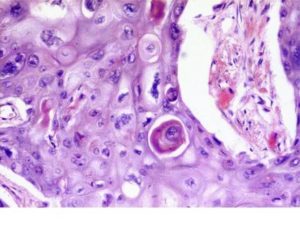

- Плоскоклеточный ороговевающий рак легкого(иначе умеренно дифференцированный плоскоклеточный рак легкого) имеет медленное развитие.

Плоскоклеточный рак бронхов и легкого этого типа характеризуется образованием так называемых раковых жемчужин. Злокачественные клетки собираются в узелки красноватого оттенка, покрытые чешуйками, в центре которых наблюдается ороговение. При раннем обнаружении прогноз самый благоприятный.